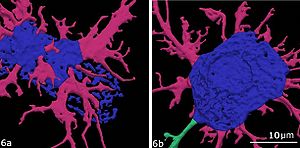

High Contrast Microstructural Visualization of Natural Acellular Matrices by Means of Phase-Based X-Ray Tomography

Publication: Sci Rep. 2015 Dec 14;5:18156. PMID: 26657471 | PDF Authors: Hagen CK, Maghsoudlou P, Totonelli G, Diemoz PC, Endrizzi M, Rigon L3, Menk RH, Arfelli F, Dreossi D, Brun E, Coan P, Bravin A, De Coppi P, Olivo A. Institution: University College London, Department of Medical Physics and Biomedical Engineering, London, UK. Background/Purpose: Acellular scaffolds obtained via decellularization are a key instrument in regenerative medicine both per se and to drive the development of future-generation synthetic scaffolds that could become available off-the-shelf. In this framework, imaging is key to the understanding of the scaffolds' internal structure as well as their interaction with cells and other organs, including ideally post-implantation. Scaffolds of a wide range of intricate organs (esophagus, lung, liver and small intestine) were imaged with x-ray phase contrast computed tomography (PC-CT). Image quality was sufficiently high to visualize scaffold microarchitecture and to detect major anatomical features, such as the esophageal mucosal-submucosal separation, pulmonary alveoli and intestinal villi. These results are a long-sought step for the field of regenerative medicine; until now, histology and scanning electron microscopy have been the gold standard to study the scaffold structure. However, they are both destructive: hence, they are not suitable for imaging scaffolds prior to transplantation, and have no prospect for post-transplantation use. PC-CT, on the other hand, is non-destructive, 3D and fully quantitative. Importantly, not only do we demonstrate achievement of high image quality at two different synchrotron facilities, but also with commercial x-ray equipment, which makes the method available to any research laboratory. Funding:

Images acquired with synchrotron-based PC-CT showing a rat small intestine that was decellularized via DET: (a) transverse cross section, (b) three-dimensional view. All scale bars represent 500 μm. Images were processed using the ESRF in-house software PyHST, and analyzed and displayed with ImageJ31 and 3D Slicer. |